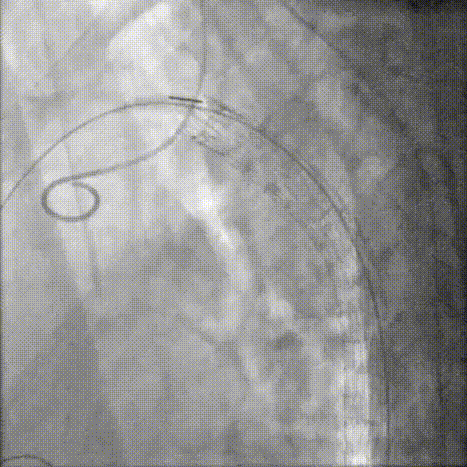

3.交换超硬导丝后置入DSF导引鞘,沿导引鞘置入GORE® TAG®可主动调控胸主动脉覆膜支架系统 TGM282815,造影确认支架位置。

gore医疗怎么样「胸有乾坤」可调可控 分毫必争—GORE®TAG® 可主动调控胸主动脉覆膜支架治疗B型主动脉夹层伴升主动脉瘤病例报道_https://www.jmylbn.com_新闻资讯_第10张

造影确认支架位置